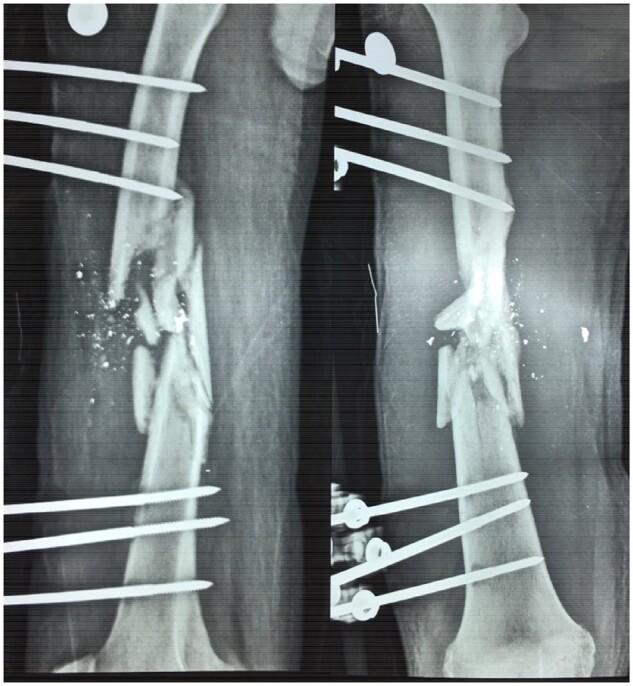

https://cdn.ncbi.nlm.nih.gov/pmc/blobs/aecb/8210113/3b77708823a9/dlz002f1.jpg